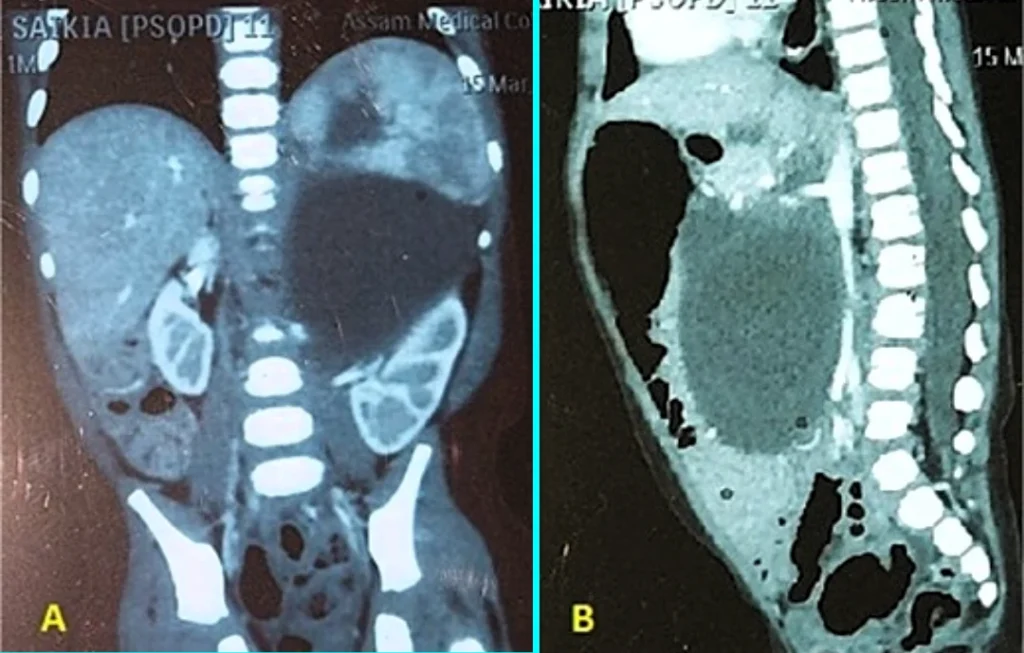

غير أن الفحص عبر التصوير الطبقي المحوري باستخدام مادة ظليلة كشف عن وجود كتلة كيسية كبيرة متعددة الحجرات، ذات جدران سميكة، كانت تضغط على الأعضاء الداخلية في البطن وتزيحها عن مواقعها الطبيعية.

وتدخل فريق جراحي متخصص لإزالة الكتلة عبر شق في الجزء العلوي من البطن، حيث جرى فصل الورم بعناية عن الأوعية الدموية الرئيسية، وإبعاده عن الكلية اليسرى والغدة الكظرية والطحال والبنكرياس وأعضاء الحوض، قبل استئصاله بالكامل بنجاح.